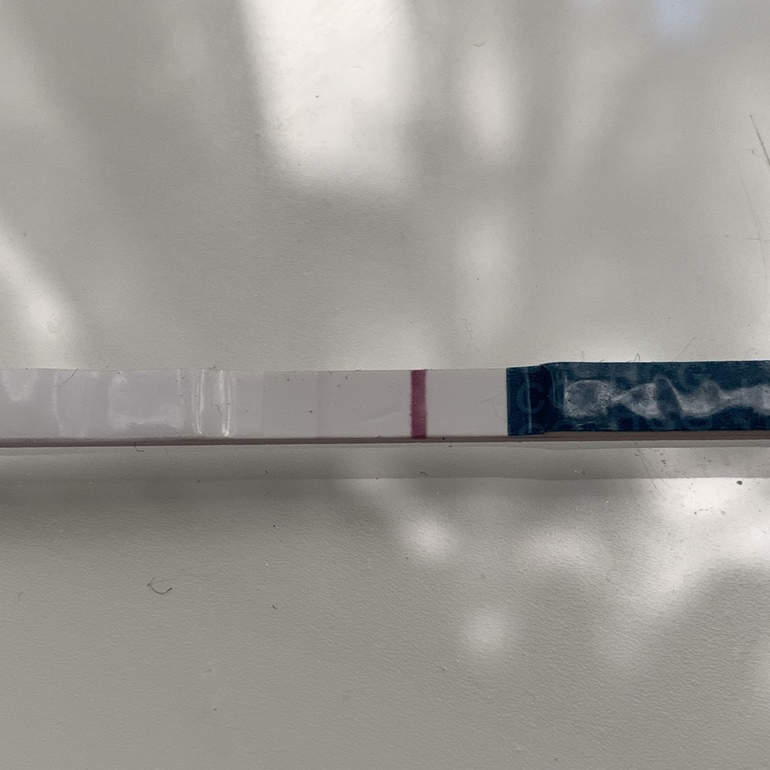

Всем привет! Сегодня 10 ДПО. Замочила тест в обед. Что думаете это ОНО самое 🥺 или реагент 🙁? Внизу фото без обработки и с фильтром. Тест эвиплан (шёл в комплекте с тестами на овуляцию).

А это уже когда тест высох!!

А это уже когда тест высох!!

Полоска то хорошая прям, явно не реагент. Да и на эви не я, не знакомые никогда не видели реагент,. Поздравляю 💐💐💐

Оно оно ! Ярчайте

Оно.у меня такая на первом тесте была, тут написали что реагент. Реагенту уже два месяца 😂

Полосочки конечно!